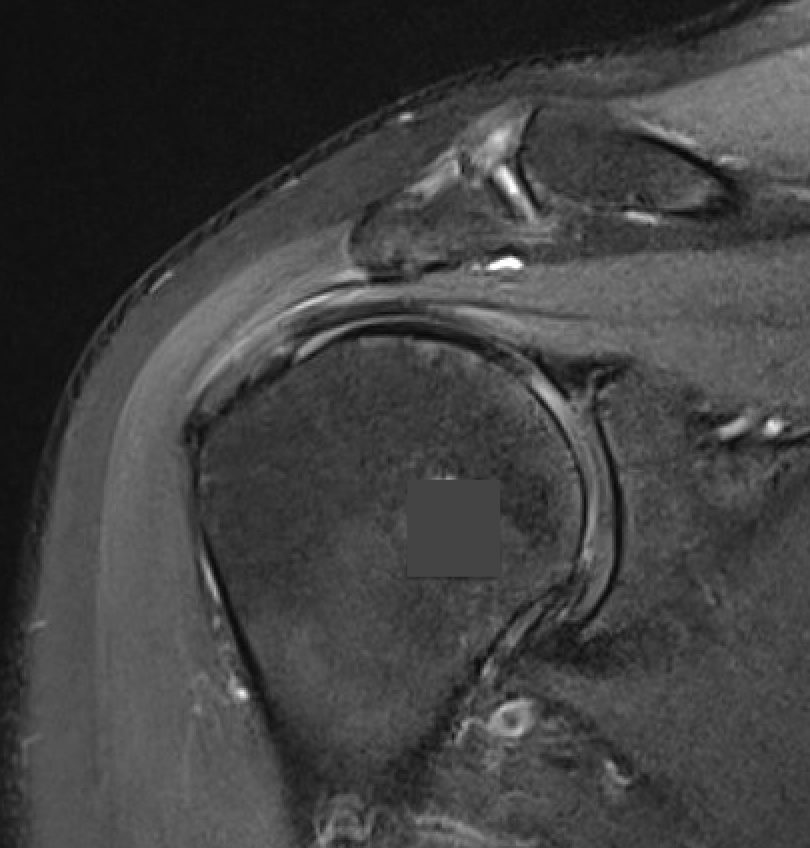

MRI

Inflammation and thickening of the rotator cuff tendons

Mild inflammation of the supraspinatus tendon insertion

Thickening and edema of the supraspinatus and infraspinatus tendon

Subscapularis tendinosis